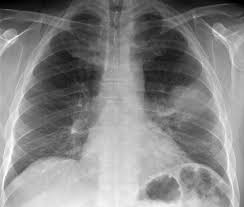

Airspace disease is considered chronic when it persists beyond 4-6 weeks after treatment. A single retrocardiac air-fluid level on a chest radiograph typically implies the presence of a sliding hiatal hernia. This unusual type of bibasilar atelectasis happens when the lung is trapped as a result of pleural disease while being devoid of air. Airspace disease also known as alveolar lung disease is a generic term thats used to describe abnormalities on chest x-ray or CT. The most common clinical causes of this CT pattern of disease include hypersensitivity pneumonitis sarcoidosis atypical infections eg those caused by Mycoplasma pneumoniae with associated bronchiolitis and acute interstitial pneumonia 25. The 2021 edition of ICD-10-CM J984 became effective on October 1 2020. J984 is a billablespecific ICD-10-CM code that can be used to indicate a diagnosis for reimbursement purposes. And retrocardiac air space disease. Retrocardiac Air Space Disease.

The location retrocardiac - behind the heart shouldnt make a difference. It is the radiological correlate of the pathological diagnosis of pulmonary consolidation. The most common clinical causes of this CT pattern of disease include hypersensitivity pneumonitis sarcoidosis atypical infections eg those caused by Mycoplasma pneumoniae with associated bronchiolitis and acute interstitial pneumonia 25. The particular way the lung collapses can often produce a. Acinar or air-space nodules. CT 5-mm slice thickness in a patient with bilateral consolidation. Tendency to coalesce near hila.